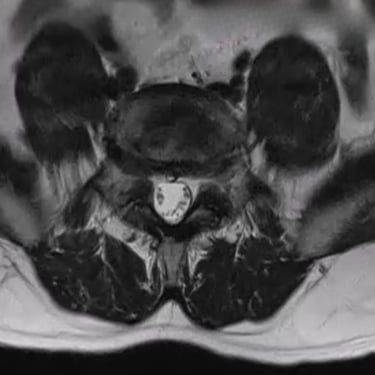

La listesis lumbar es el deslizamiento de una vértebra sobre otra, que puede causar dolor lumbar, rigidez y compresión nerviosa con irradiación hacia las piernas. Su diagnóstico se basa en estudios de imágenes de columna vertebral, principalmente radiografías dinámicas (flexión y extensión) que permiten evaluar la estabilidad segmentaria. La resonancia magnética (RMN) complementa el estudio al mostrar el grado de compresión neural y las alteraciones discales asociadas. En casos avanzados, la tomografía ayuda a valorar el compromiso óseo. Un diagnóstico preciso es esencial para determinar el tratamiento adecuado, desde medidas conservadoras hasta la cirugía de estabilización vertebral.